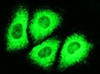

Помощь в поиске лекарства против вирусного гепатитаУпомянутая клеточная культура представлена клетками печени человека, биологическое поведение ничем не отличается от клеток, инфицированных ВГС.

Это первая эффективная модель, адекватно отображающая инфекционный процесс при ВГС, говорит доктор Мартина Брук (Martina Buck), доцент Калифорнийского университета, Сан-Диего, являющаяся одним из разработчиков культуры клеток. Потребность в разработке новых лекарственных средств чрезвычайно высока, продолжает доктор Брук, и теперь исследователи могут максимально достоверно воспроизвести процессы, происходящие при болезни.

Вирус гепатита С передается через внутривенные инъекции и половым путем. На сегодня не существует животной модели инфекционного процесса, в которой можно было бы испытать новые лекарства, а единственная эффективная терапия – препараты пегилированного интерферона-альфа – оказывает ожидаемый эффект лишь в 50% случаев. Новый метод позволит ученым исследовать течение ВГС на человеческих клетках, то-есть, ожидаемые результаты будут иметь наивысшую на сегодня достоверность.